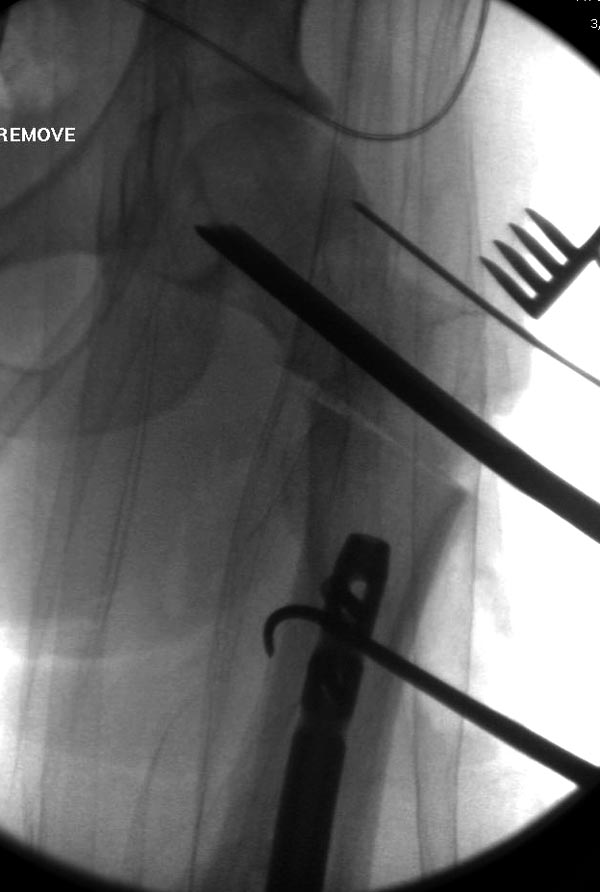

закончилась смертью трех остальных“боевых комрадов”. Начатую коллегой

открытую операцию на шейке пришлось закончить мне, установкой винтов и

ретроградной фиксацией бедра. Выписка в обычное сроки и наблюдался

несращения! По истечению 4 месяцев появились признаки варусной

деформации. На СТ срезах несращение шейки и бедра. Риминг, замена на

более толстый гвоздь и вальгусная остеотомия.